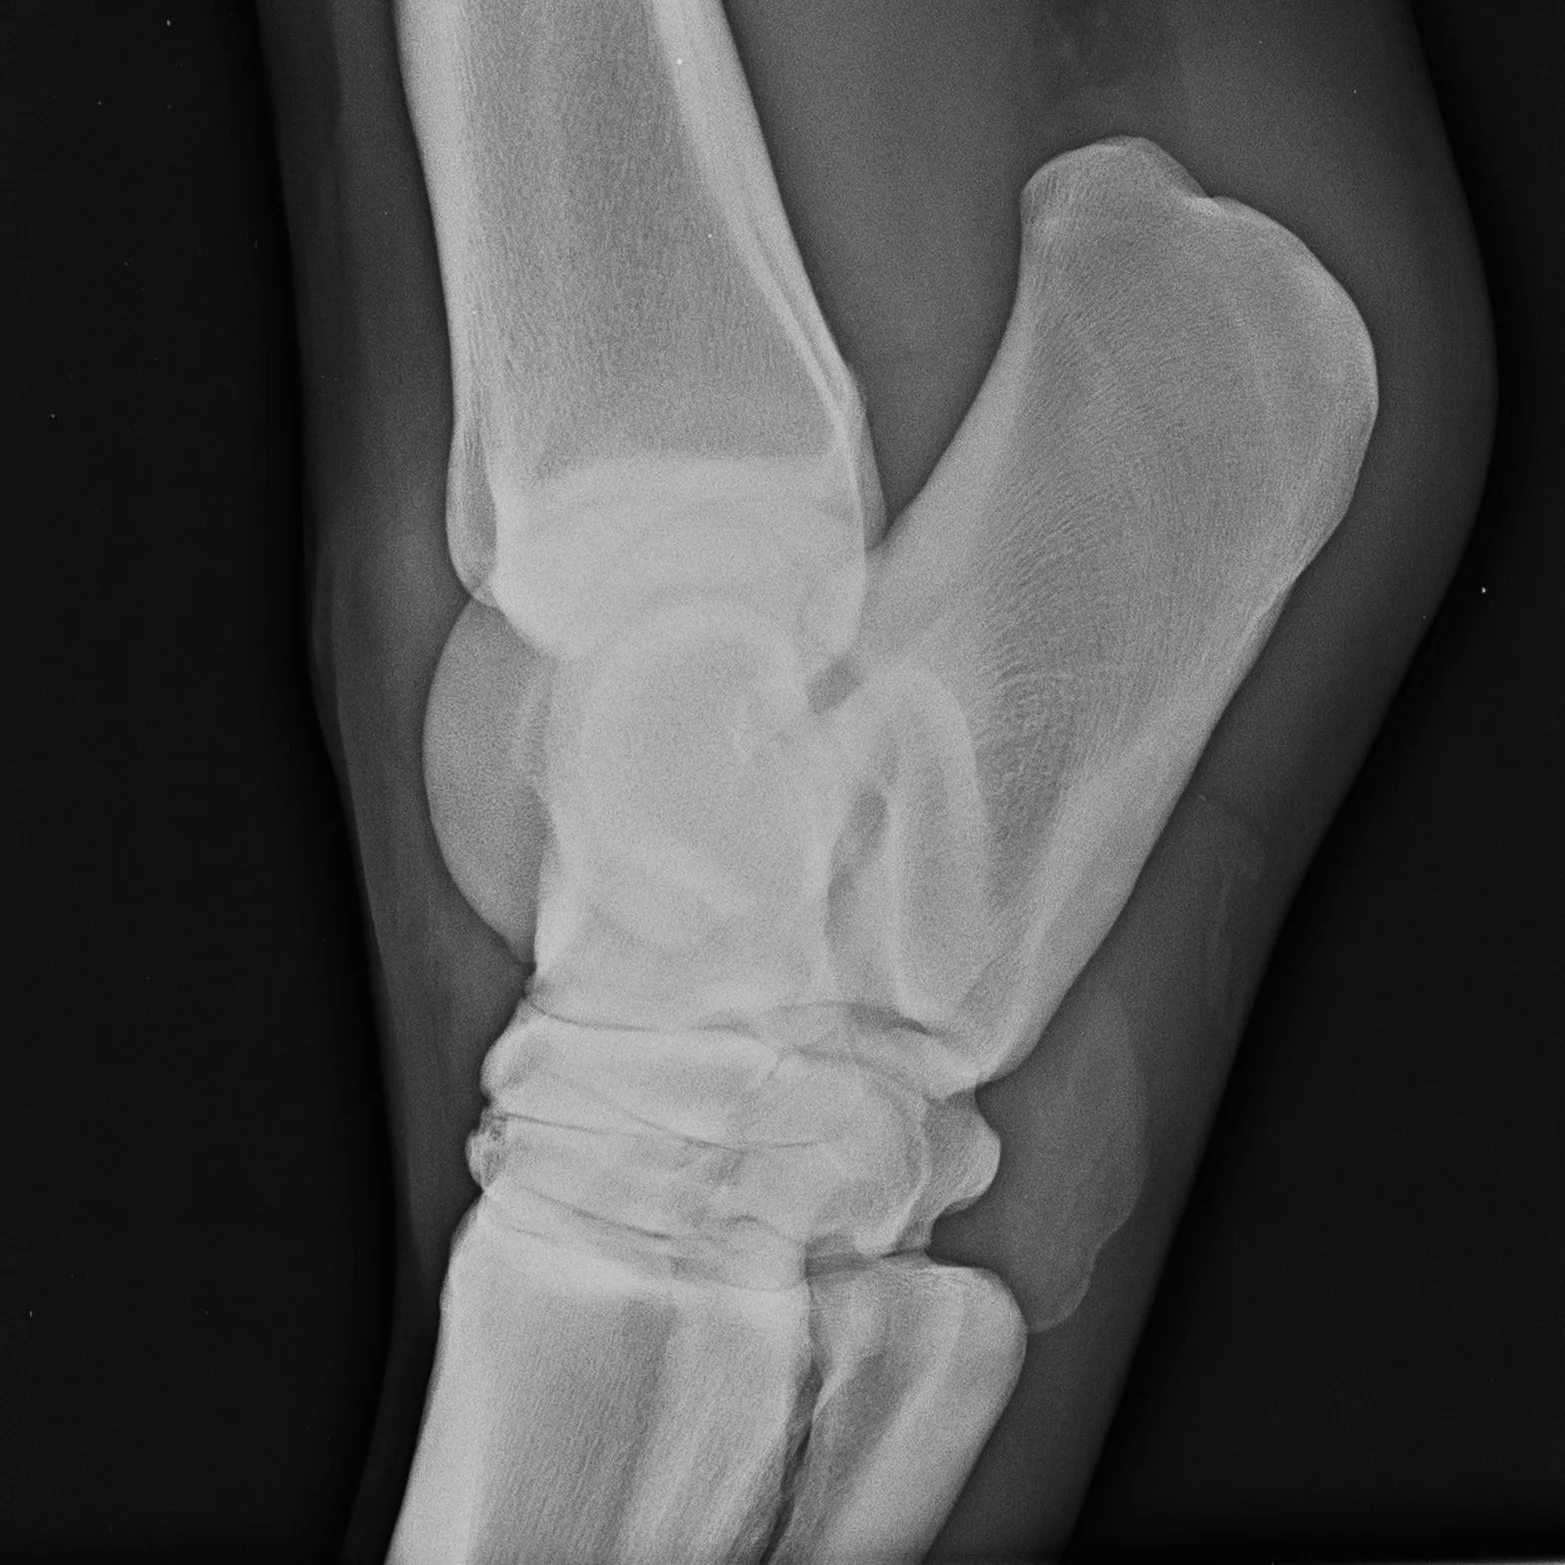

X ray horse

X ray horse 133 фото